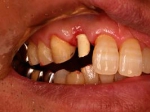

片側2歯欠損 主訴-入れ歯を使ってみたが違和感強くてダメ。固定のものにしたい。術前下顎口腔内(鏡像)

術前口腔内(正面観)